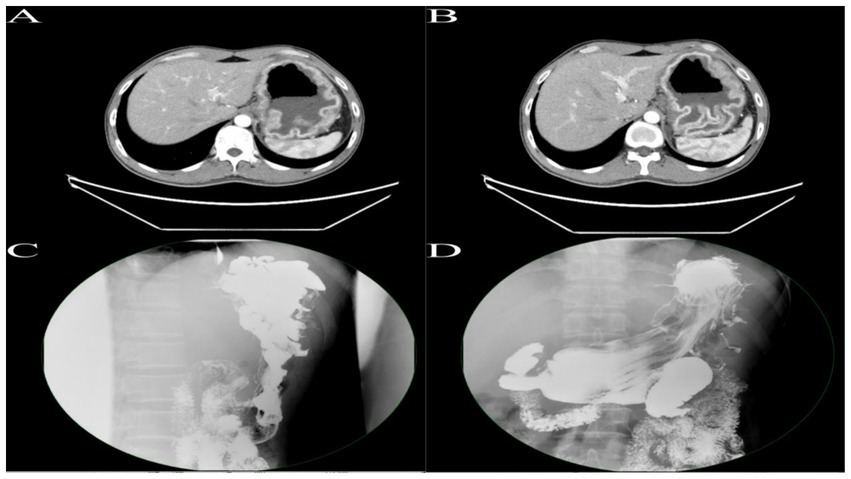

After admission, upper gastrointestinal contrast study and contrast-enhanced CT of the chest, abdomen, and pelvis confirmed the diagnosis of Menetrier’s disease involving the gastric fundus and body (Figure 1). Multidisciplinary discussion determined the lesion was too extensive for ESD, recommending surgical intervention with total gastrectomy. Following preoperative optimization and exclusion of surgical contraindications, and in accordance with the patient’s wishes, robot-assisted total gastrectomy with Roux-en-Y esophagojejunostomy was planned.

Figure 1. (A,B) Enhanced CT of the upper abdomen reveals gastric distension with significant mucosal thickening exhibiting a corrugated appearance, with pronounced enhancement on contrast imaging. (C,D) Upper gastrointestinal series demonstrates marked hypertrophy of the mucosal folds in the fundus and body of the stomach, presenting with polypoid and convoluted characteristics, with some interfold spaces appearing irregular.